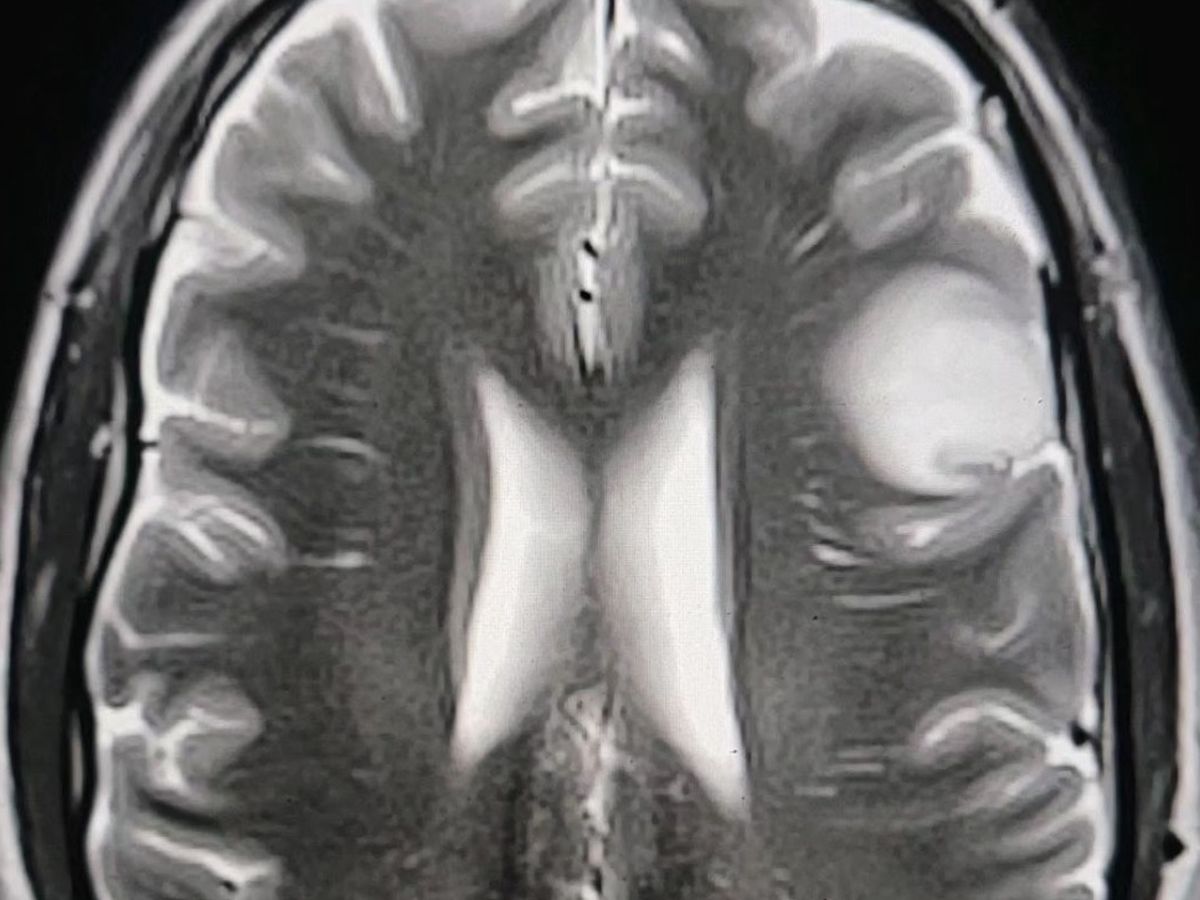

Hi! I’m Rachel's sister (kind of) and wanted to start this to try to help them with a lot of unexpected costs they are facing currently and in the next couple of months. They recently found out that Tony has a frontal left lobe glioma brain tumor that will require an awake craniotomy. They have found a great team of doctors and surgeons in Kansas City that have a plan. Only a few surgeons in the country specialize in this area of the brain where Tony’s tumor is located and one happens to be here! At the moment Tony is experiencing focal seizures throughout the day and they are trying to stabilize him to be able to do the tests and scans needed to prepare for surgery.